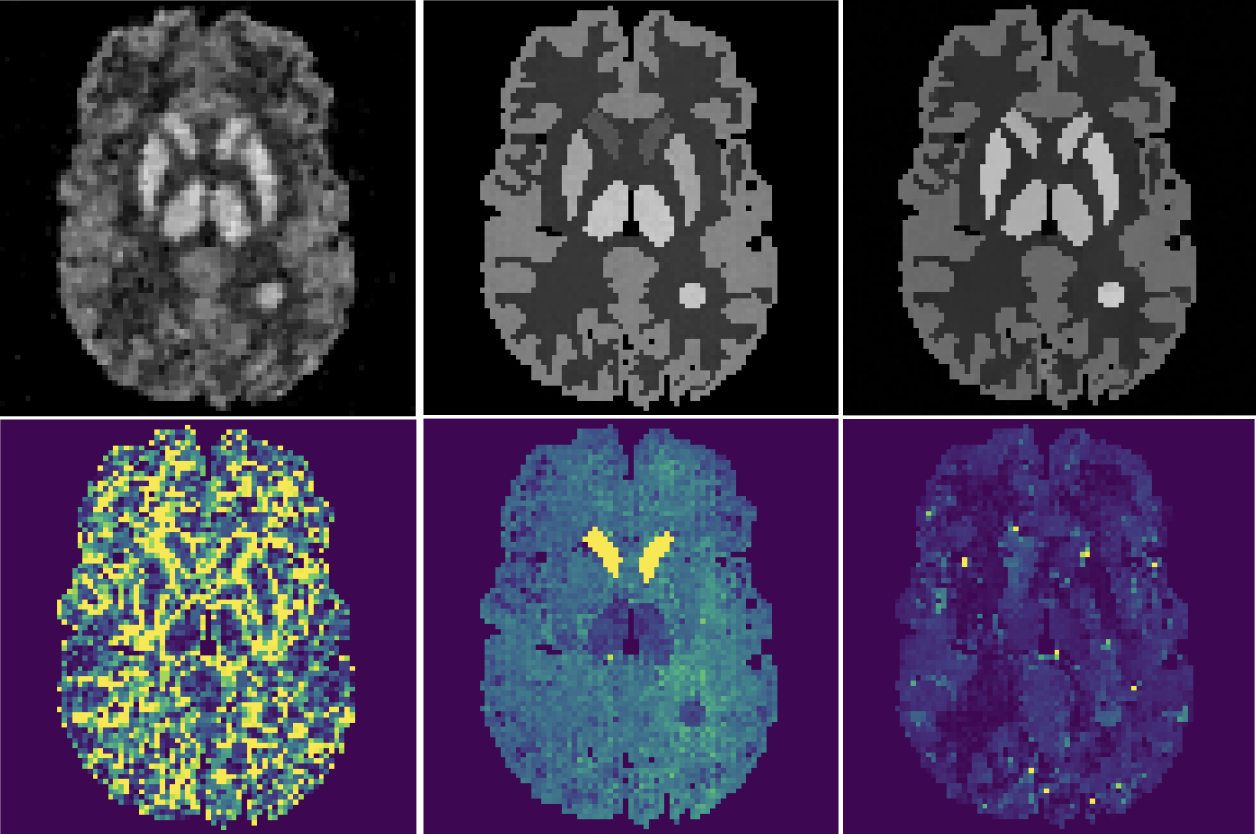

- Formulated PET (Positron Emission Tomography) reconstruction as a Bayesian inference problem.

- Applied Normalizing Flows (RealNVP, Glow) to model the posterior distribution of tracer activity.

- Implemented a Deep Probabilistic Imaging pipeline, enhancing reconstruction accuracy and providing crucial uncertainty estimates for clinical diagnosis.

- Scaled training with multi-GPU parallelization (3.7x speedup) while maintaining image quality.